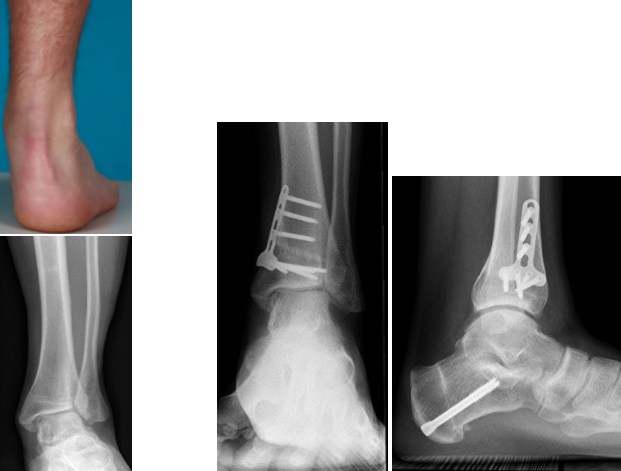

Calcaneusosteotomie (Fersenbein)

Die Fersenbeinkorrektur stellt eine der am häufigsten durchgeführten knöchernen Korrekturen an der unteren Extremität dar. Hauptsymptom ist meistens eine ausgeprägte Fehlstellung des Fersenbeins. Dadurch entsteht ein Überlastungssyndrom mit Entwicklung von Schmerzen. Mittelfristig resultiert die Fehlbelastung häufig in der Entstehung von Abnützungen der Rückfußgelenke.

Supramalleoläre Osteotomie (auf Knöchel-Niveau)